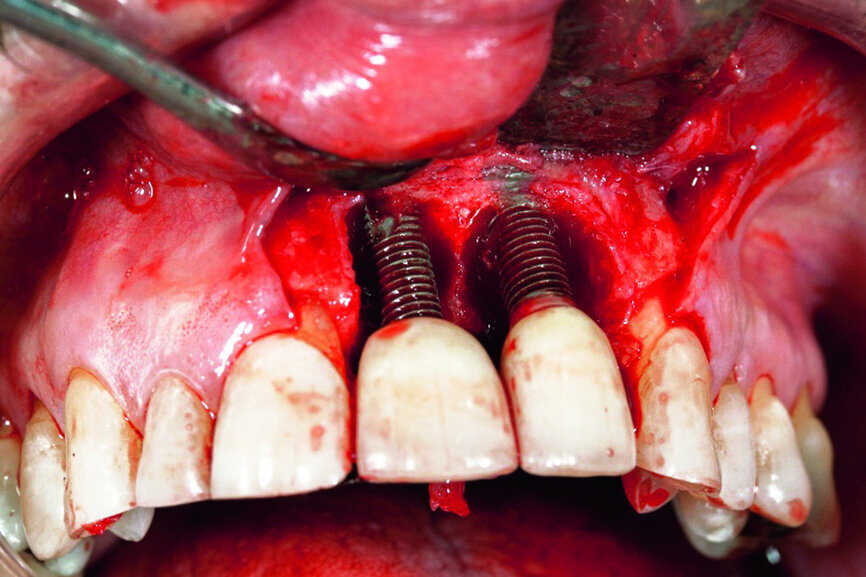

In accordance with the described protocol, a mucoperiosteal flap was created in order to obtain full access to the severe four-wall defect (Fig. 3). The implant surface was mechanically cleaned with diamond-coated burs (Fig. 4). Chemical debridement of the surface with subsequent antibiotic impregnation was performed (Figs. 5 & 6).